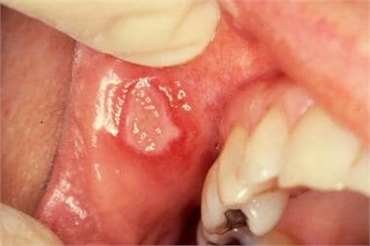

Major aphthous ulcers are also known as Sutton's disease. These ulcerations can occur at any age. They have an acute onset. This type of ulcer is painful initially but decreases gradually. A major aphthous ulcer is 1 to 3 cm in diameter. It is deeper than minor aphthous ulcers. The major aphthous ulcers are present in groups (1 to 10) and take 2 to 6 weeks to heal. They occur mostly after puberty.

Major aphthous ulcers are usually seen on the labial (gums approximating the front teeth) mucosa, soft palate and tonsils. These ulcerations are usually associated with lymph node enlargement. The margins or edges of these ulcers are inflamed. The base of these ulcers is not fixed. The size of these ulcerations can interfere with speech and eating. These lesions leave a scar after healing which leads to a localized destruction tissue in that area. Recurrent episodes of major aphthous ulcers may continue for 20 years after the first episode.

In a major aphthous ulcer, the patient might have prodromal burning. This means that there is itching and stinging for nearly 48 hours, after which the ulcer begins to grow for the next 72 hours. The lesion has a reddish hue which is at times covered by greyish membrane.